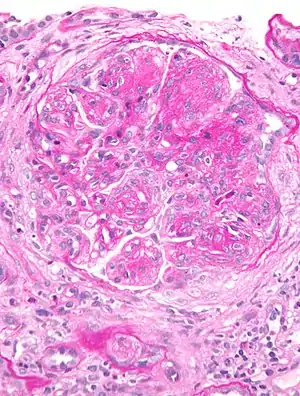

Micrograph of glomerulus in membranoproliferative glomerulonephritis with increased mesangial matrix and increased mesangial cellularity. Kidney biopsy. PAS stain. | |

The GBM is rebuilt on top of the deposits, causing a "tram tracking" appearance under the microscope.[6] Mesangial cellularity is increased.[7]